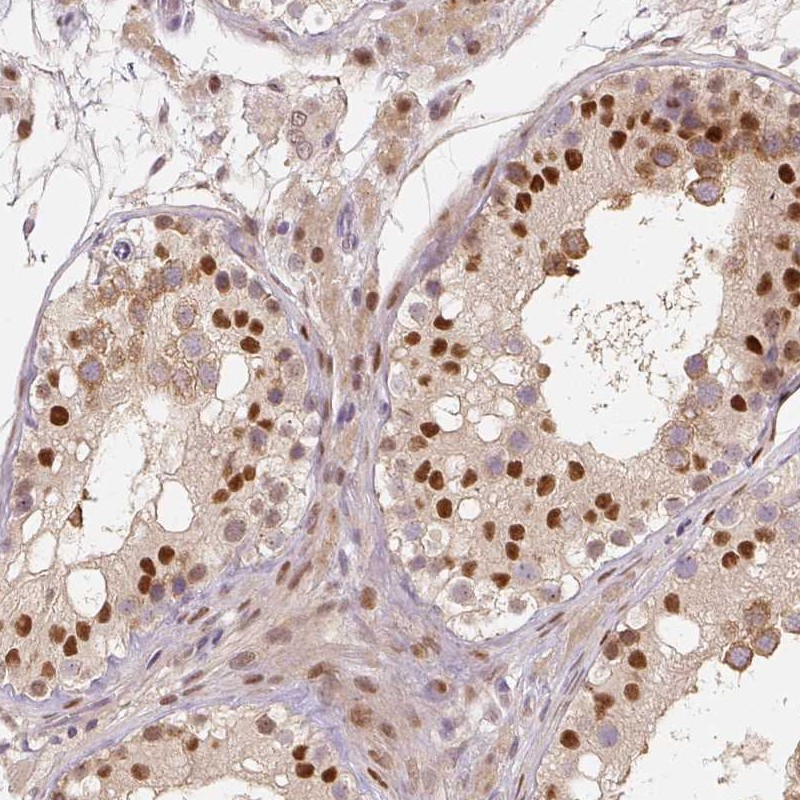

Immunohistochemical staining of human testis shows strong nuclear positivity in a subset of cells.